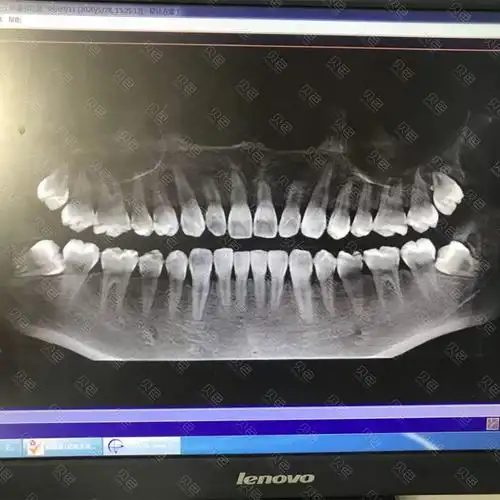

去年治牙拍的牙片,大家看我有智齿吗?

我也来晒晒我的牙片请大佬来看看07怎么样

每个人都有必要去牙科拍牙片检查一下,说不定就有小惊喜 - 贝色口腔

【口腔微学院】拍摄牙片您需要知道的一些事